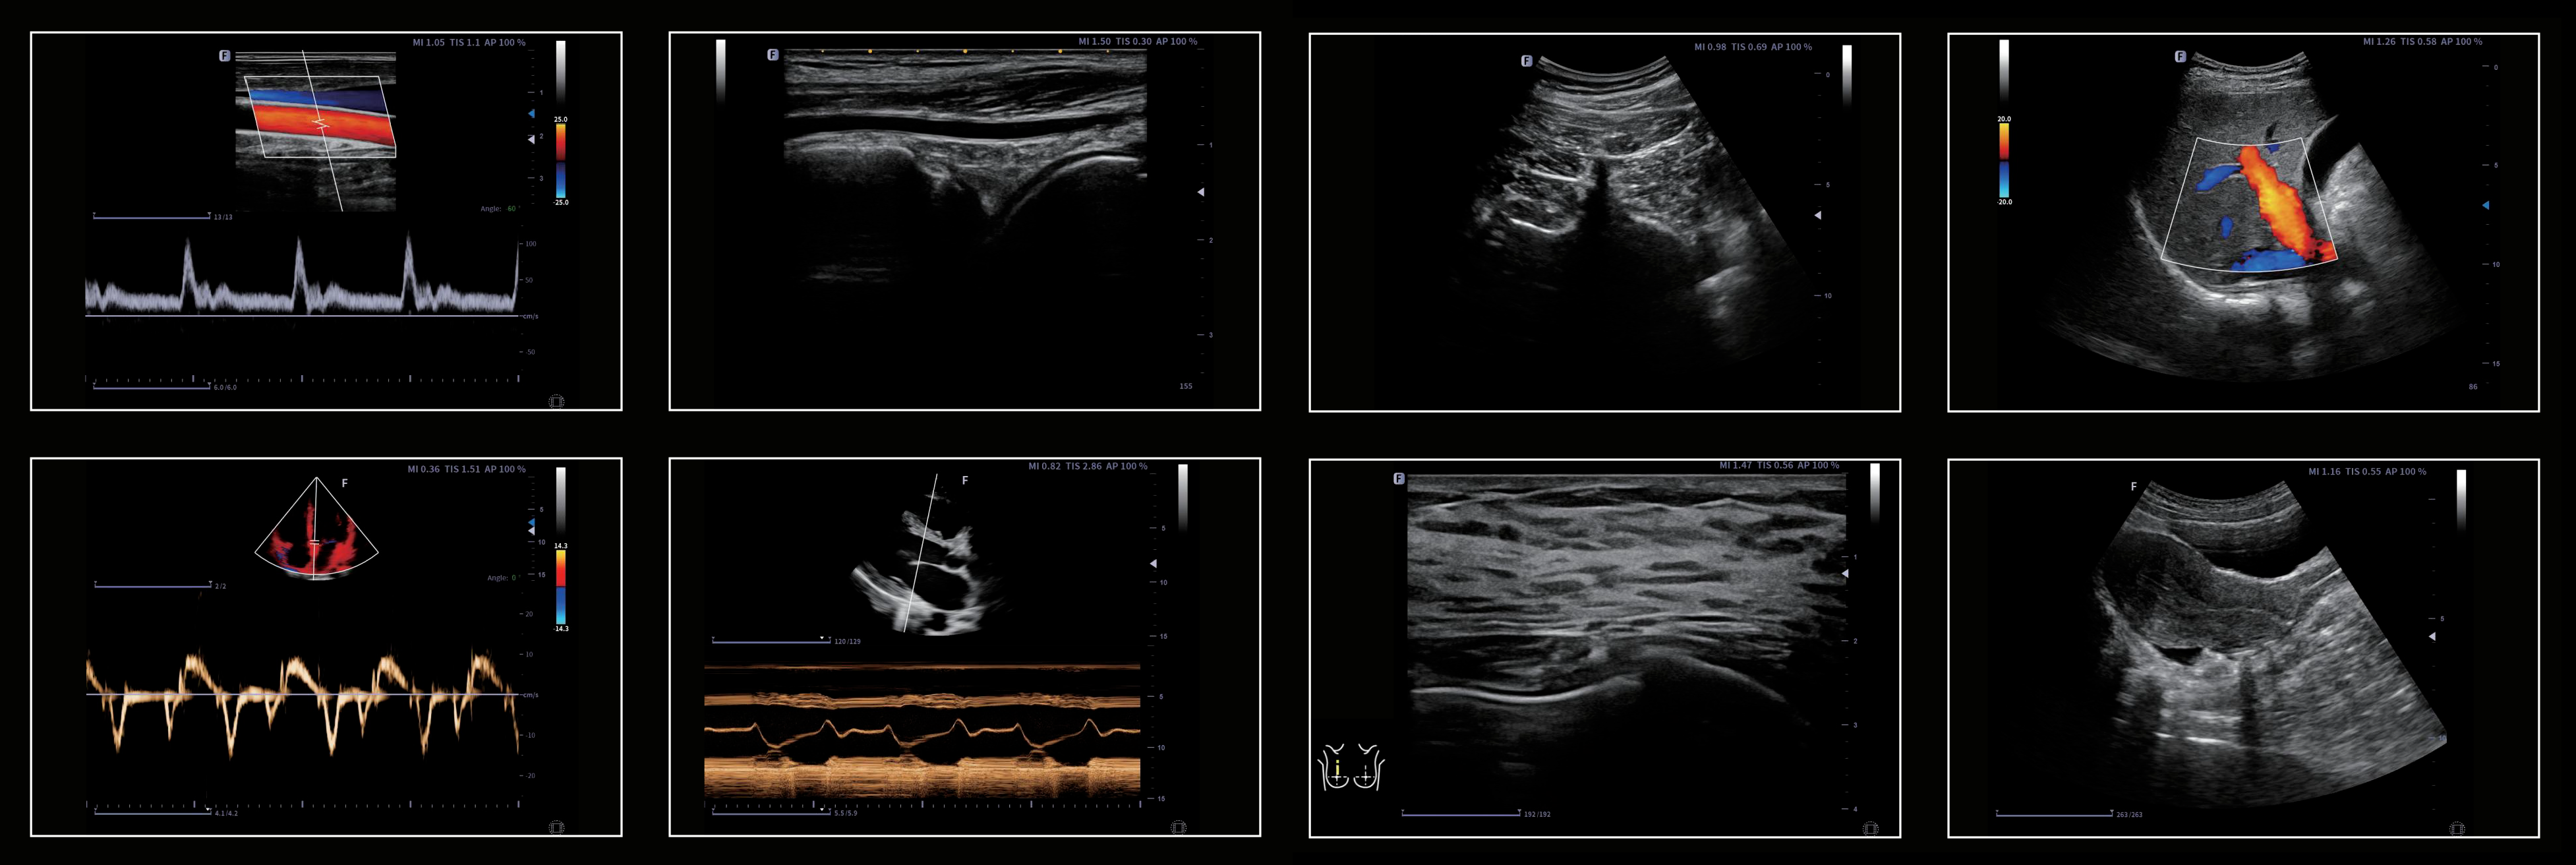

Finus 50’s unique imaging technologies and transducer

technology provide users with detailed images to

enhance thier diagnosis confidence.

Excellent Clinical Images